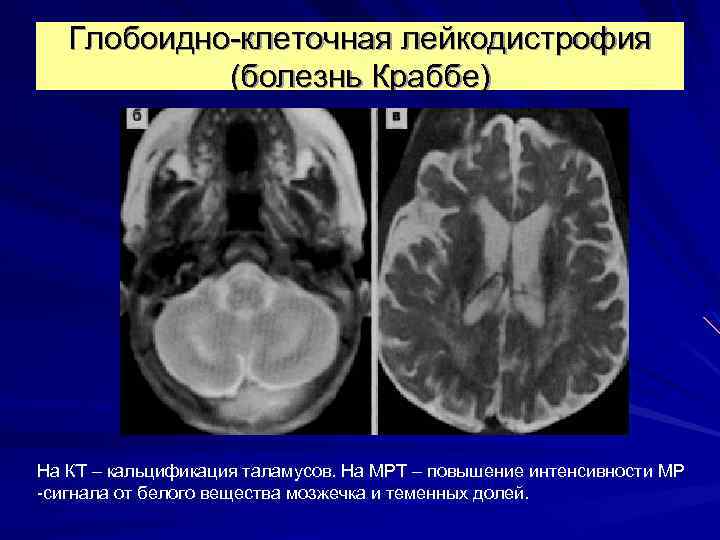

Глобоидно-клеточная лейкодистрофия (болезнь Краббе) На КТ – кальцификация таламусов. На МРТ – повышение интенсивности МР -сигнала от белого вещества мозжечка и теменных долей.